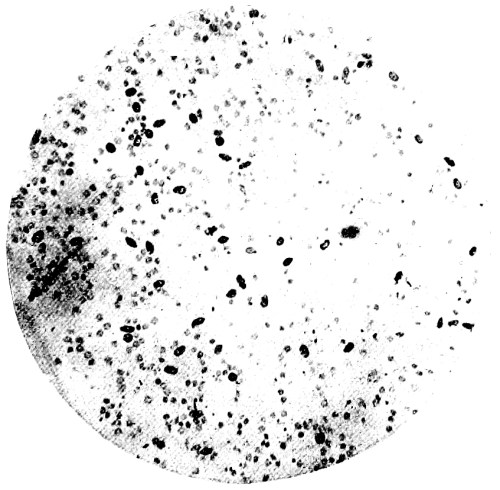

10. Photo-micrograph of Red Blood Corpuscles from Domestic Fowl 99

11. Photo-micrograph of Blood Corpuscles of Fish 99

12. Photo-micrograph of Blood Corpuscles from a Dried Stain of the Blood of a Cod-fish 100

13. Photo-micrograph of a Frog‘s Blood showing oval nucleated Red Corpuscles 101

14. Photo-micrograph of Crystals of Hæmin 102